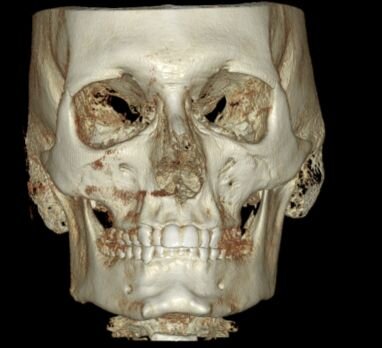

I need some advice! I have a deep and distal bite, and I've been thinking about bimax or lefort surgery, but my orthodontist said that it can be fixed with braces without surgery. The plan is to move the upper teeth slightly back and the lower teeth slightly forward to correct the bite, but I'm worried that moving the upper teeth will also move my maxilla, which is already flat. Should I be concerned about this? I want to receive valuable advice from experienced and knowledgeable individuals.

I can take any necessary measurements of the bones.

I can take any necessary measurements of the bones.